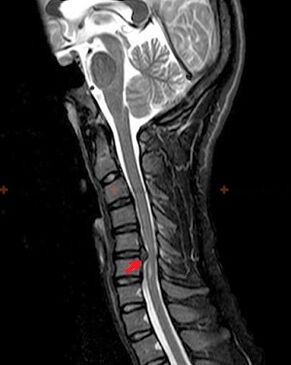

The following research methods are used to diagnose osteochondrosis: radiography (preferably with functional tests), MSCT and MRI.The latter study is the most preferred due to the fact that it allows to visualize very clearly the state of the intervertebral structures.

The presence of the changes described above, as well as the changes in the structure of the intervertebral disc detected by MSCT and MRI, serve as reliable signs confirming the presence of osteochondrosis.